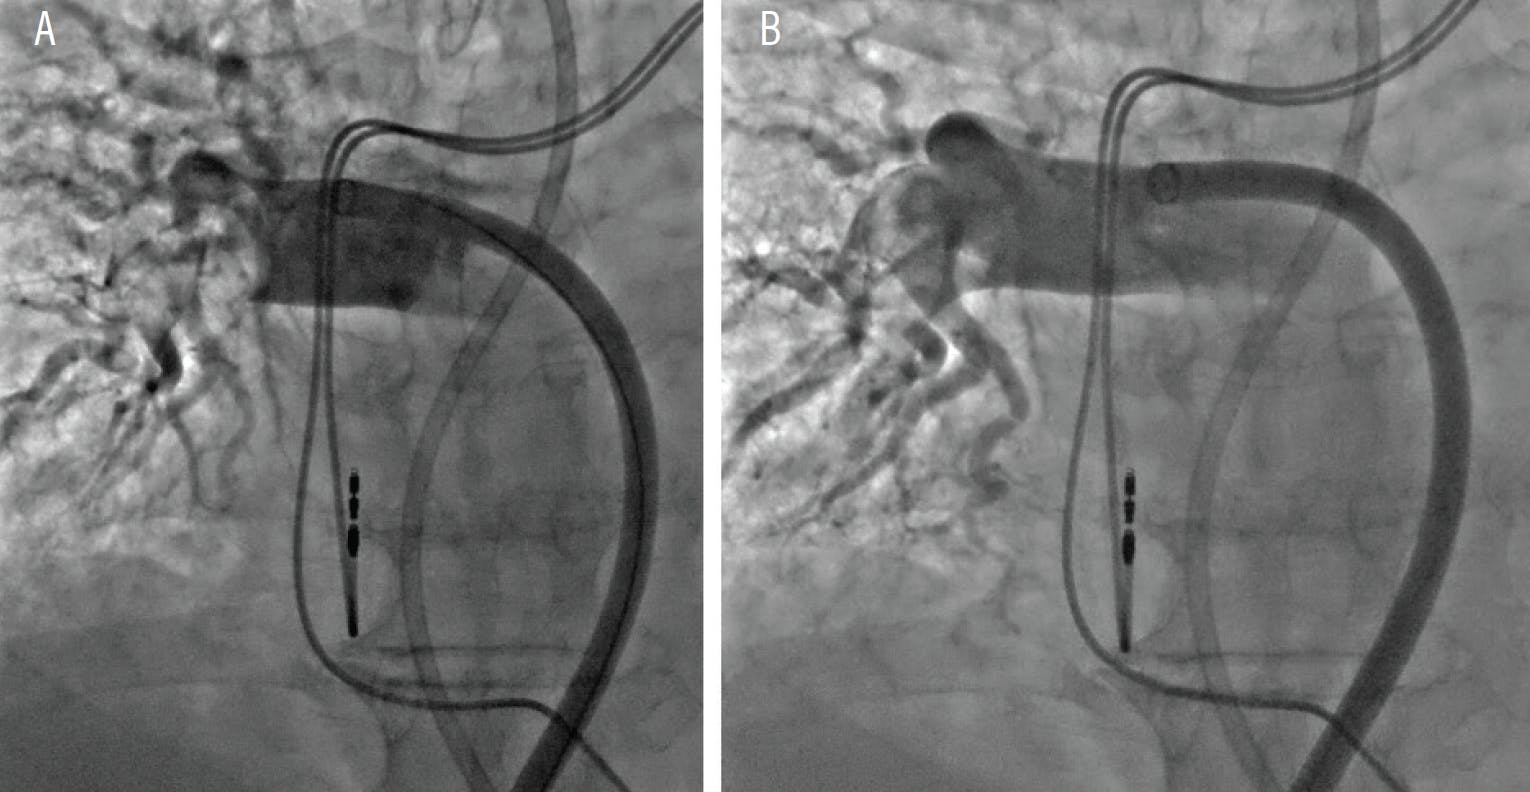

Indigo aspiration system.  The Indigo aspiration system was introduced almost simultaneously as the FlowTriever, initially as a means for mechanical aspiration of clot from peripheral arteries and veins and later adopted for the treatment of PE. The initial 8-F CAT8 Indigo device was evaluated in the EXTRACT-PE trial (Table 1), which studied 119 patients with submassive PE who underwent mechanical thrombectomy. There was significant reduction in RV/LV ratio at 48 hours and complications were infrequent.25 In contrast to the FlowTriever, the intention of this catheter was to mostly remove lobar thrombus in hopes of re-establishing distal perfusion and thus improving oxygenation and hemodynamics (Figure 3).26

Figure 3. Selective angiogram of the right PA demonstrated a large PE (A). Selective angiogram postthrombectomy demonstrating significant thrombus resolution (B).